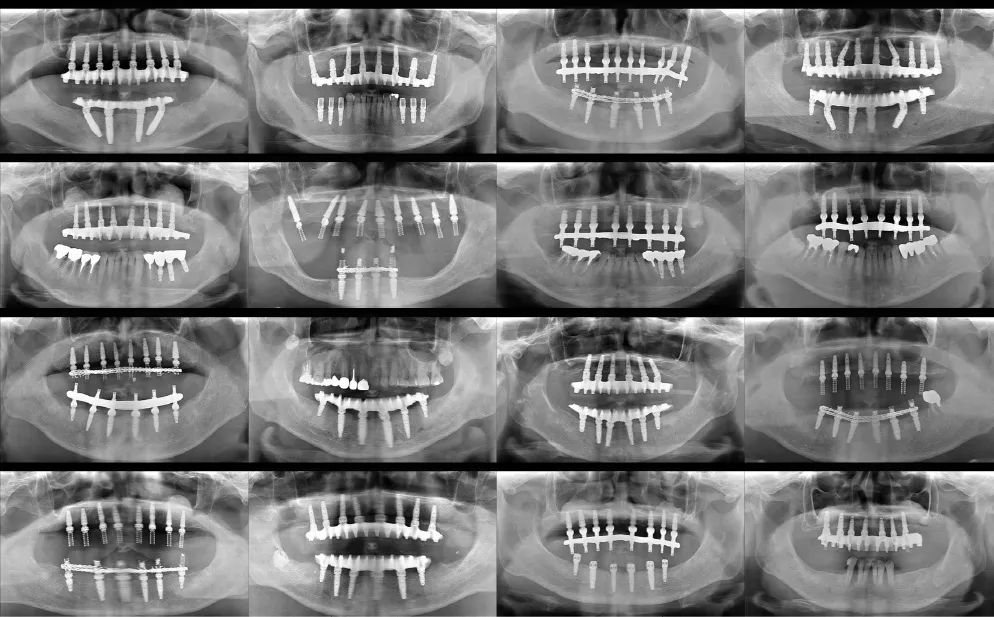

当院では、日本口腔インプラント学会をはじめとした、種々の学会・公的機関の治療指針を尊重することで、過去の事実に裏付けされた、安全性の高い治療計画を立案します。

いまだ多くの歯科医療機関が未対応な中、当院では2000年代より全患者様に無償で提供しています。

当院では、治療の正確性、安全性を高めるために、治療の難易度に関係なく全てのケースでサージカルガイドを無償でご用意し、手術に臨みます。

骨の量が原因で治療を断られてしまった方でも、正確な診断と高度な技術による骨造成を行うことでインプラント治療を受けられる可能性があります。

当院は骨造成処置に対応

骨造成は、難易度が高く治療技術と経験が問われるため、実際に高い成功率を持って治療を行える歯科医師はごくわずかです。

中部地方の中核インプラント施設として、インプラントの難しい症例に対応してきました。各地の歯科医療機関様よりご依頼を受けて、難しい骨造成症例の解決に取り組んでおります。